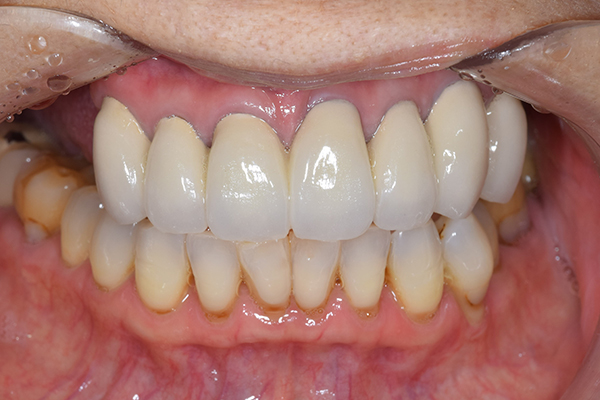

こちらが完成したかぶせ物と入れ歯です。かぶせ物にはアタッチメントをつけて金属のバネが見えない構造になっています。 入れ歯自体も金属を使用して、極力違和感がでないように、薄く作成しました。

お口の中に入れた状態です。 非常に見た目もよい出来となりました。 バネがみえないと見栄えが全然ちがいます。

見た目が入れ歯とわからない様に針金のない、アタッチメントを使用した入れ歯を作成することにしました。